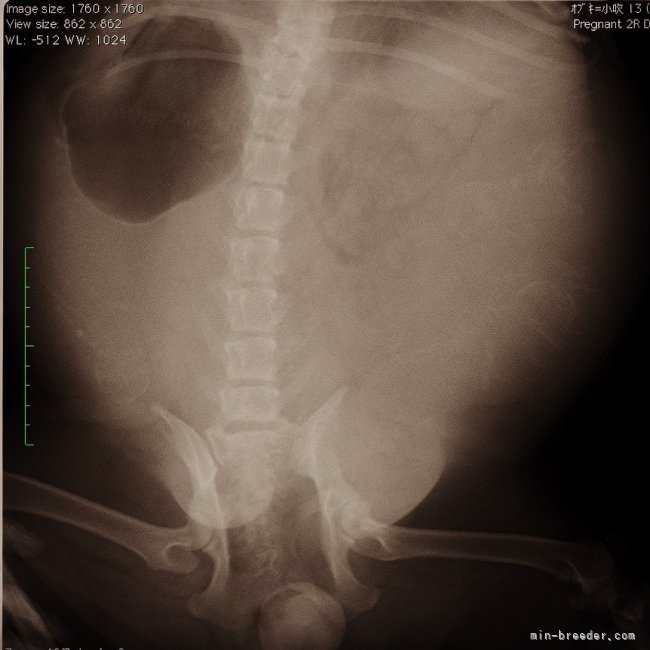

てんちゃんレントゲン🩻撮影しました❣️

5頭かなぁ〜?

いて、6頭って感じです🤭

とりあえず、今の時点ではみんな元気に心臓が動いておりました‼️☺️

しかし、奇形の多い犬種😢

口蓋裂などエコーやレントゲン撮影では見えない疾患も沢山あります🥺💦

てんちゃんの赤ちゃん達がみんな無事でありますように(>人<;)🙏

もちろんてんちゃんも‼︎